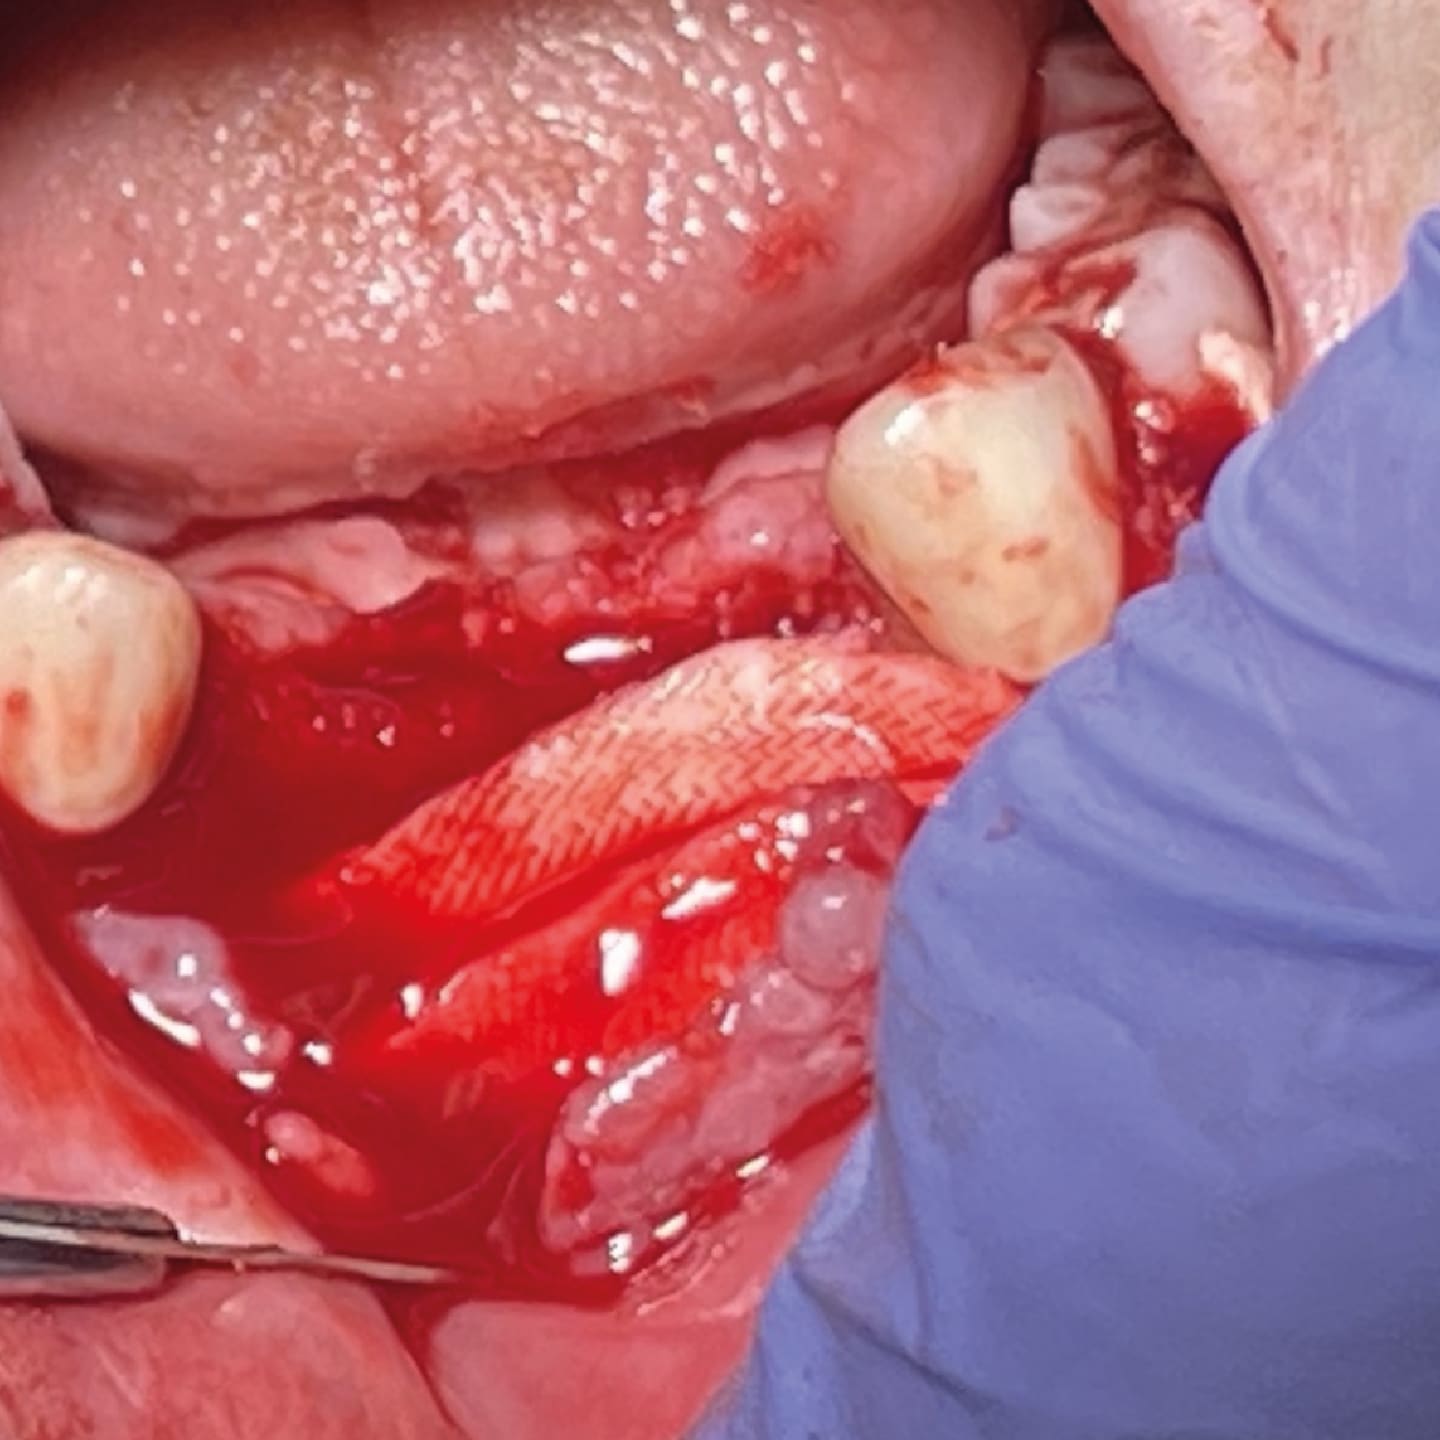

The gingiva was edematous and erythematous, and the sutures were prematurely unraveling, exposing underlying bone and the threads of the implant (Figure 9). Under local anesthesia with lidocaine and epinephrine 1:100,000, a full-thickness flap was reflected over the anterior mandibular ridge from approximately canine to canine, revealing multiple exposed threads on both implants with severe facial bone loss on implant No. 26 (lower right lateral incisor). Because the No. 23 implant (lower left lateral incisor) was stable and had fewer facial threads exposed, it offered the possibility of guided bone regeneration to retain the implant (Figure 10). Implant No. 26 was explanted due to rapid loss of bone on the facial and the likelihood that GBR was not an option (Figure 11). The anterior ridge was decorticated to increase vascularity, and a 50:50 mixture of calcium apatite and freeze-dried demineralized bone was placed over the ridge and in the explanted socket (Figure 12).

ADM was used as a barrier membrane for guided bone regeneration because there was insufficient gingival tissue to achieve primary closure of the grafted ridge. The ADM, while occlusive, ultimately breaks down to a mesh, allowing nutrients to pass through its pores while still serving as a barrier during the healing phase (Figure 13).